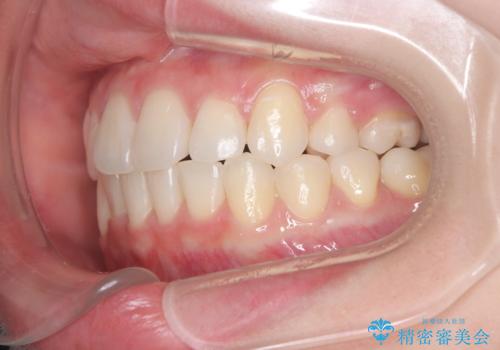

- 患者様は、下顎両側の第1大臼歯(6番)と右上6番の欠損を主訴に来院されました。

通常であればインプラントによる補綴が第一選択となる症例でしたが、患者様ご自身がインプラントを希望されなかったため、矯正治療によって欠損部の閉鎖を図る方針としました。

ワイヤー矯正を用いて、欠損部の閉鎖を目的とした後方からの歯の挺出・移動を行いました。

特に、親知らずを活用し、奥歯の噛み合わせを構築することに重点を置きました。

最終的には予定通りインプラントを使用せずに欠損部を閉鎖し、咬合も安定させることができました。